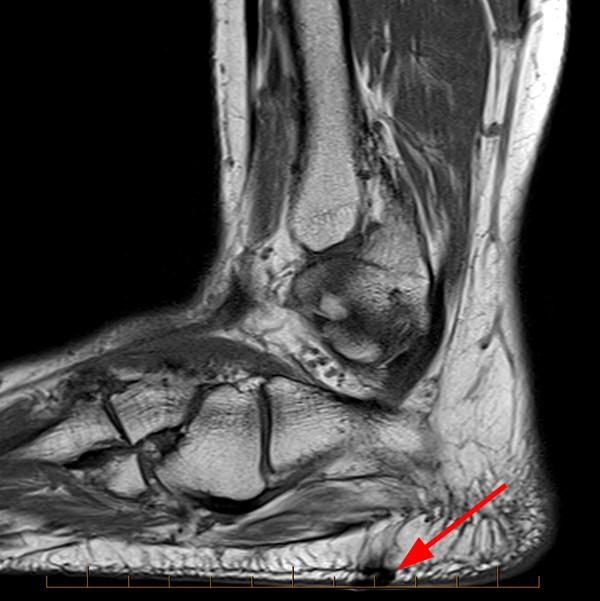

Baxter's Nerve Mri . Magnetic resonance imaging (mri) may be used to detect alterations associated with adq muscle denervation (18,26). Mri can show if the muscles have hypertrophied around it, causing some compression of that nerve, as well as compression of the nerve does create some fluid and inflammation around that nerve and some thickening of the fascia itself. An mri can show where fatty atrophy of the abductor digiti quinti muscle strongly indicates baxter’s nerve entrapment. Baxter's nerve is vulnerable to entrapment because of its course, and the most common location is the tight fascia of the abductor hallucis and the medial aspect of the quadrates plantae muscle. This imaging test can reveal the accumulation of fatty edema, as well as the likely atrophy of the involved. It is a common cause of heel pain and is often. The most reliable test for baxter’s neuropathy is an mri scan. Tarsal tunnel syndrome is characterized by an entrapment of the posterior tibial nerve in the foot.

Magnetic resonance imaging (mri) may be used to detect alterations associated with adq muscle denervation (18,26). The most reliable test for baxter’s neuropathy is an mri scan. Tarsal tunnel syndrome is characterized by an entrapment of the posterior tibial nerve in the foot. It is a common cause of heel pain and is often. Baxter's nerve is vulnerable to entrapment because of its course, and the most common location is the tight fascia of the abductor hallucis and the medial aspect of the quadrates plantae muscle. An mri can show where fatty atrophy of the abductor digiti quinti muscle strongly indicates baxter’s nerve entrapment. Mri can show if the muscles have hypertrophied around it, causing some compression of that nerve, as well as compression of the nerve does create some fluid and inflammation around that nerve and some thickening of the fascia itself. This imaging test can reveal the accumulation of fatty edema, as well as the likely atrophy of the involved.